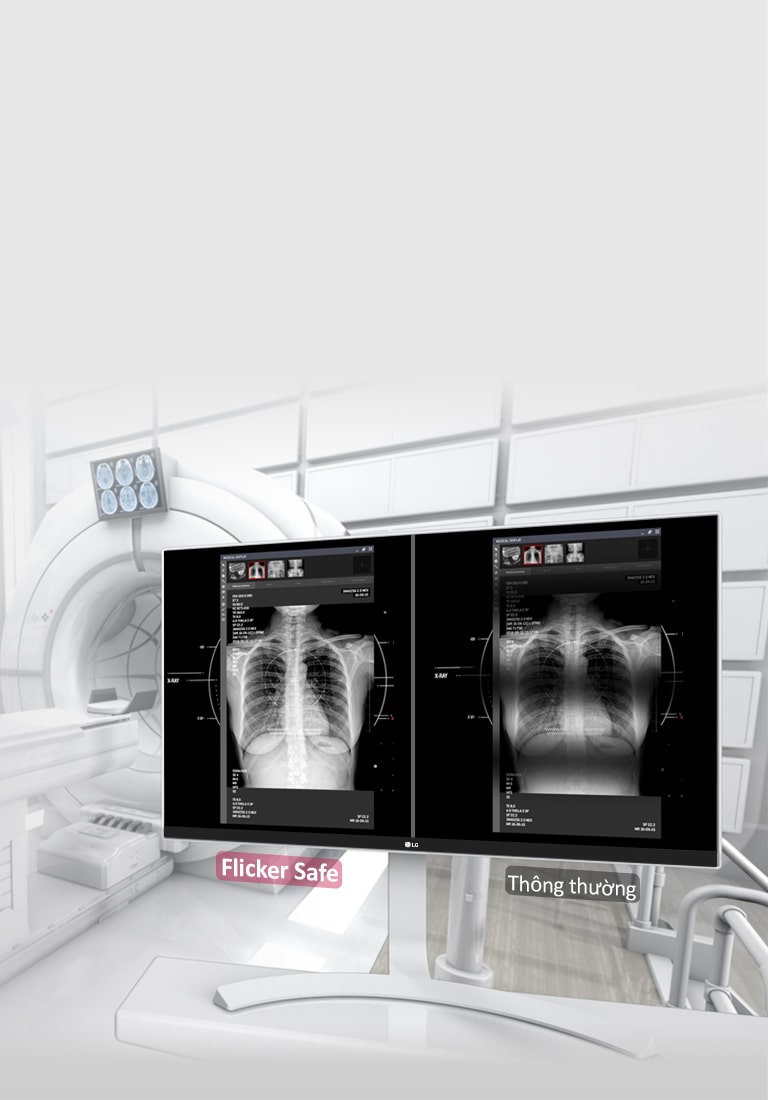

Chống nháy hình

CÓ